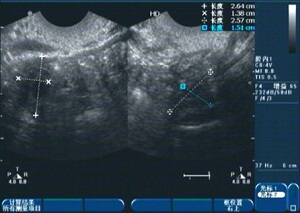

1、診斷:醫(yī)生會(huì)通過(guò)詢問(wèn)病史、體檢及輔助檢查(如超聲檢查、激素檢測(cè)等)來(lái)確定診斷。